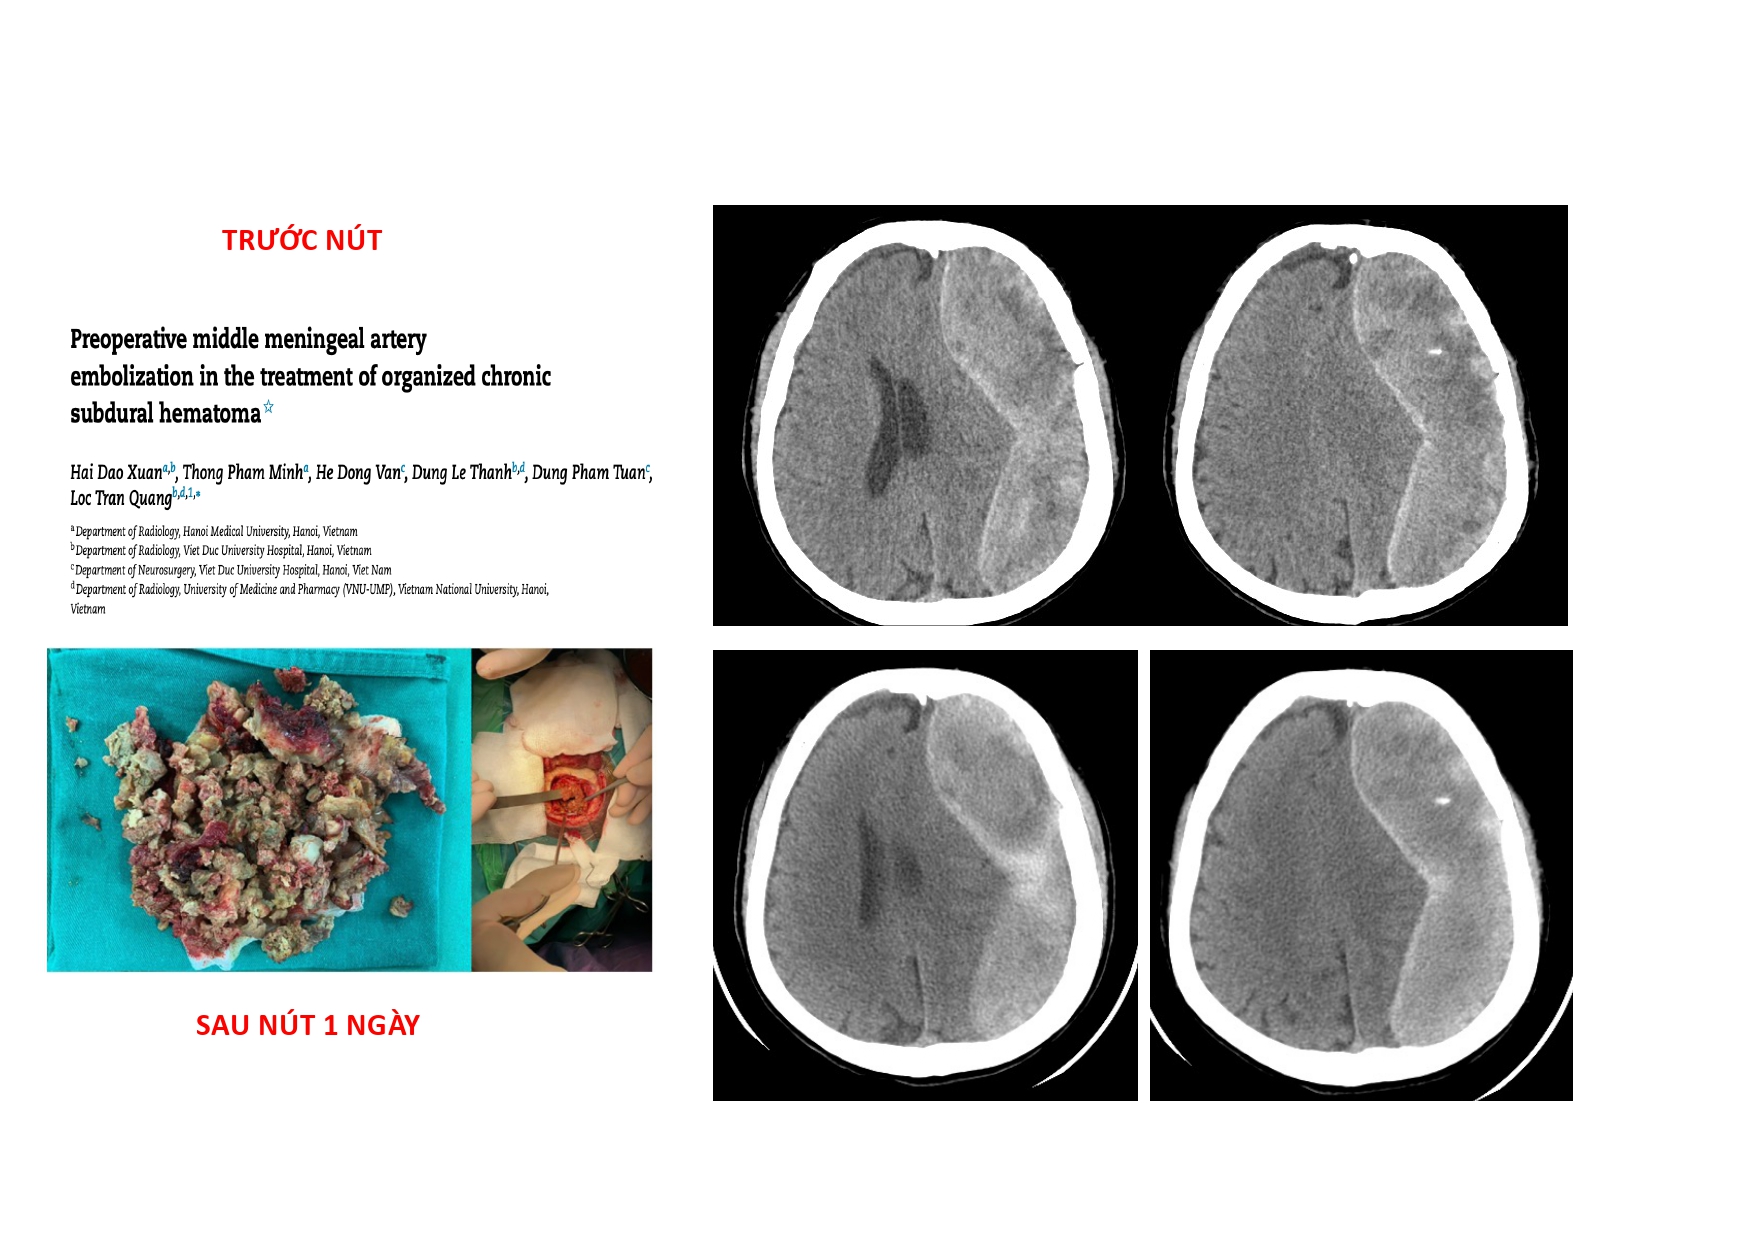

| 14:10 - 15:10 | DEBATE 2 | Recurrent chronic subdural hematoma– surgical or endovascular intervention? Surgical: Assoc. Prof. Duong Dai Ha Endovascular: Assoc. Prof. Le Thanh Dung | Moderator: Prof. Christian Matula Assoc. Prof. Duong Dai Ha | |